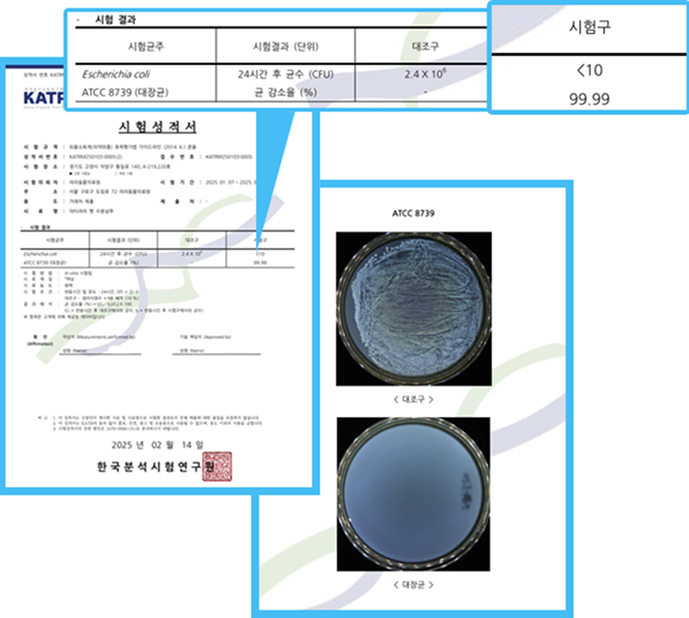

Dr.Lala宠物保湿洗发水的抑菌能力如何?

✅金黄色葡萄球菌/大肠杆菌 99.99%!

- 金黄色葡萄球菌认证书 -

- 金黄色葡萄球菌认证书 - - 大肠杆菌认证书 -

- 大肠杆菌认证书 -

- 球菌、马拉色菌认证书 -

- 球菌、马拉色菌认证书 -